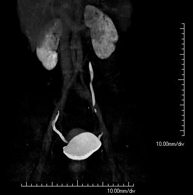

- TC Dental

Prueba radiológica que consiste en obtener imágenes de los huesos maxilares de alta definición anatómica (piezas dentarias, trayecto del nervio dentario), mediante el empleo de un equipo de TC (Tomografía Computarizada). Indicaciones: estudio previo a la extracción dental, estudio previo a implantes, tumores, absceso.